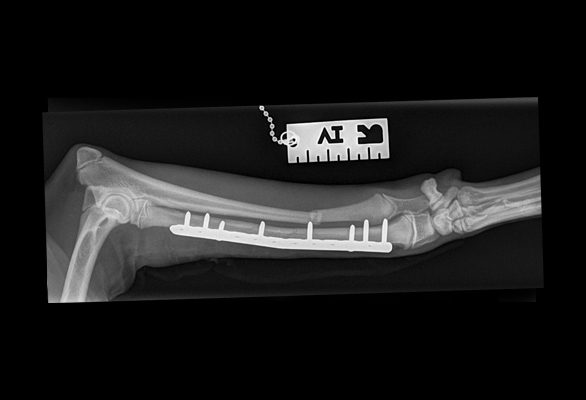

Surgery aims to realign and stabilise the fractured bones to allow uneventful healing. There are numerous methods used to stabilise the fractured bone including the use of plates, screws, pins, and wire. These are hidden from view and placed under the skin (internal fixation).

Fixator surgery

Fixators, both linear (straight) and circular may also be used to temporarily stabilise the bone whilst healing, and these are visible externally (external fixators).

Drag the circle to view before and after surgery images.